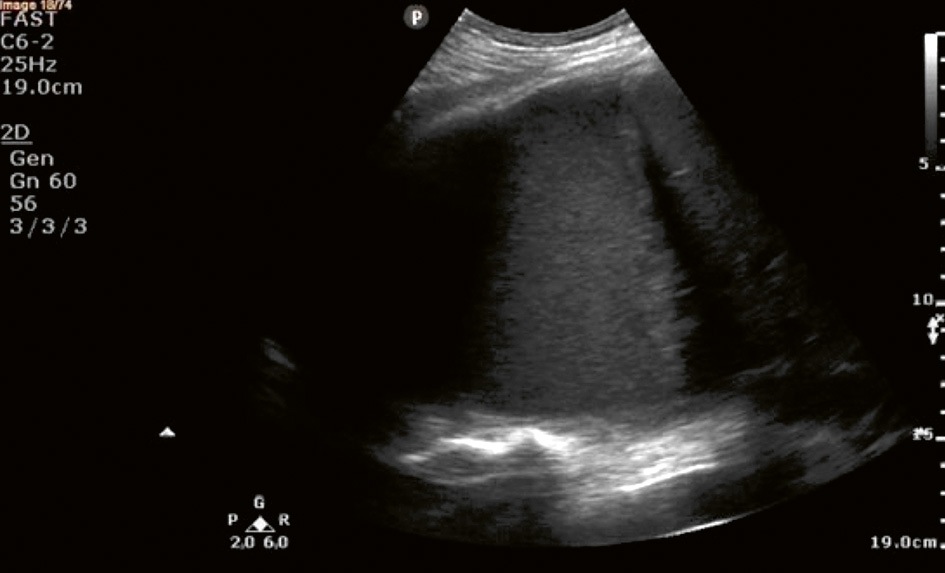

Sonografiskt utseende av pleuravätska (A–D). Pleuravätska identifieras med ultraljud som ett spatium mellan pleura parietale och pleura viscerale [48] och kategoriseras enligt ekogenitet och innehåll [49].

A. Anekoisk–homogen svart pleuravätska (1) hos en 65-årig kvinna med hjärtsvikt. I bilden ses kotpelaren på djupet, så kallat »spine sign« (2), och atelektatisk lunga simmande fritt i vätskan, så kallat »jellyfish sign« (3) [50]. Aorta (4) syns också tack vare pleuravätska.